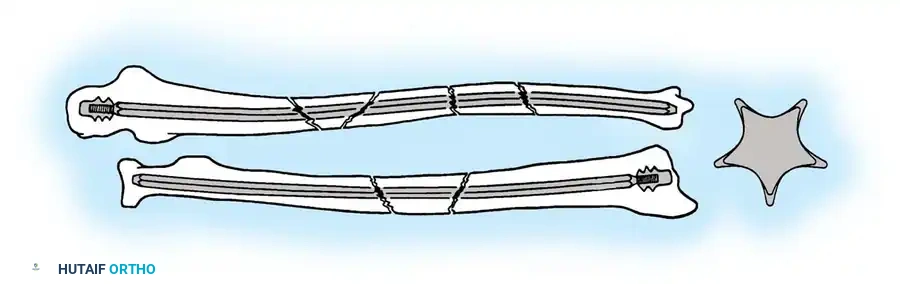

Fig. 54-53 A and B, Simple loop is not as satisfactory as figure-of-eight loop for fixing fracture of olecranon. C, Simple loop is insufficient when its long axis is in or anterior to long axis of olecranon.

Fig. 54-54 Internal fixation of olecranon with tension band wire loop. Wire passed through hole drilled in distal fragment and through triceps aponeurosis adjacent to bone. Figure-of-eight loop adds stability to fracture and prevents distraction and posterior bowing.

Fig. 54-55 Olecranon fracture repaired with long 6.5-mm AO cancellous screw and figure-of-eight tension band wire loop. Screw must engage cortex of diaphysis of ulna.

Fig. 54-56 A and B, Transverse olecranon fracture repaired with Kirschner wires and tension band technique. C, Double twist modification of wiring suggested by Weber and Vasey.